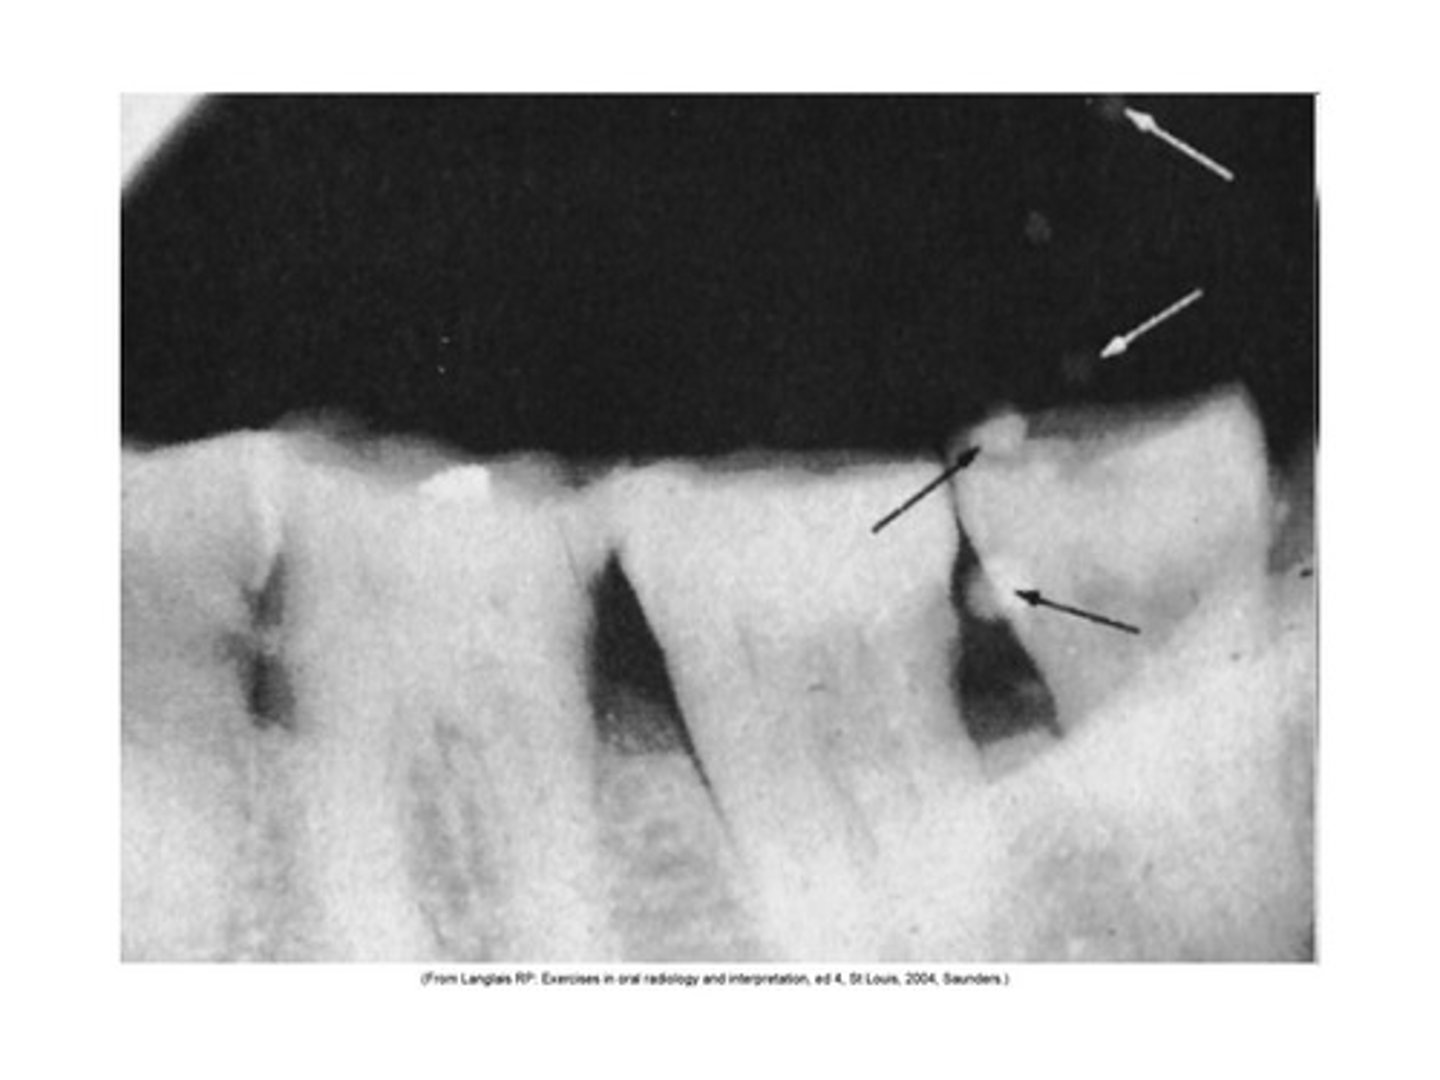

Apical cut-off

Overlapping